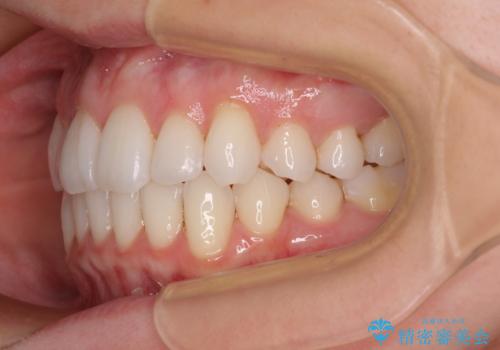

【モニター】インビザラインで気になるデコボコと八重歯をきれいに整える

- 上下前歯のデコボコ、特に右上の八重歯を気にして来院された患者様です。

治療後半では悪阻によりマウスピースの装着時間が不十分となることもありましたが、それよりも前にしっかりと装着時間を守って治療を進めることができたため、特に気になるところなく治療を終えることができました。